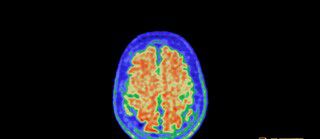

운동과 식단으로 치매를 예방하자

귀하신 몸(교육방송1 토 밤 9시45분) 치매를 예방할 수 있을까? 치매는 공포의 불치병으로 알려졌는데 충분히 막을 수 있다고 한다. 그에 도움이 되는 효과적인 운동법과 식단을 소개한다. 2022년 기준 대한민국 전국 치매 환자 수 약 93만명. 65살 이상 인구 10명 중 1명은 치매를 앓고 있다. 한 60대 남성은 매일 소주 한병을 마시고 담배 반갑을 피우다 치매 전 단계인 경도인지장애 진단을 받았다. 80대 남성은 2019년 치매 판정을 받은 이후 현재까지 일상생활을 잘 유지하고 있다. 두 사례를 통해 치매 전후 관리법을 알아본다. 이 외에도 치매 구분법, 치매 치료의 골든타임, 가짜 치매, 치매 예방을 위한 운동과 식단, 중년기 치매 예방법까지 치매에 대해 심층적으로 다룬다.